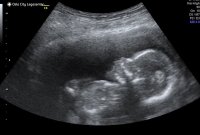

Nub teorien er vel fra tidligst 12 uker. Før det er det stor sjangs for at nub'en "reiser seg", altså at det ser ut som jentevinkel og så blir det guttSlenger meg påSyns det ser ut som jente på meg, men er vel mer troverdig etter uke 12. Var 11+4 her. Spurte om å få filme litt, og da var det lettere å lete etter nubben i sakte film